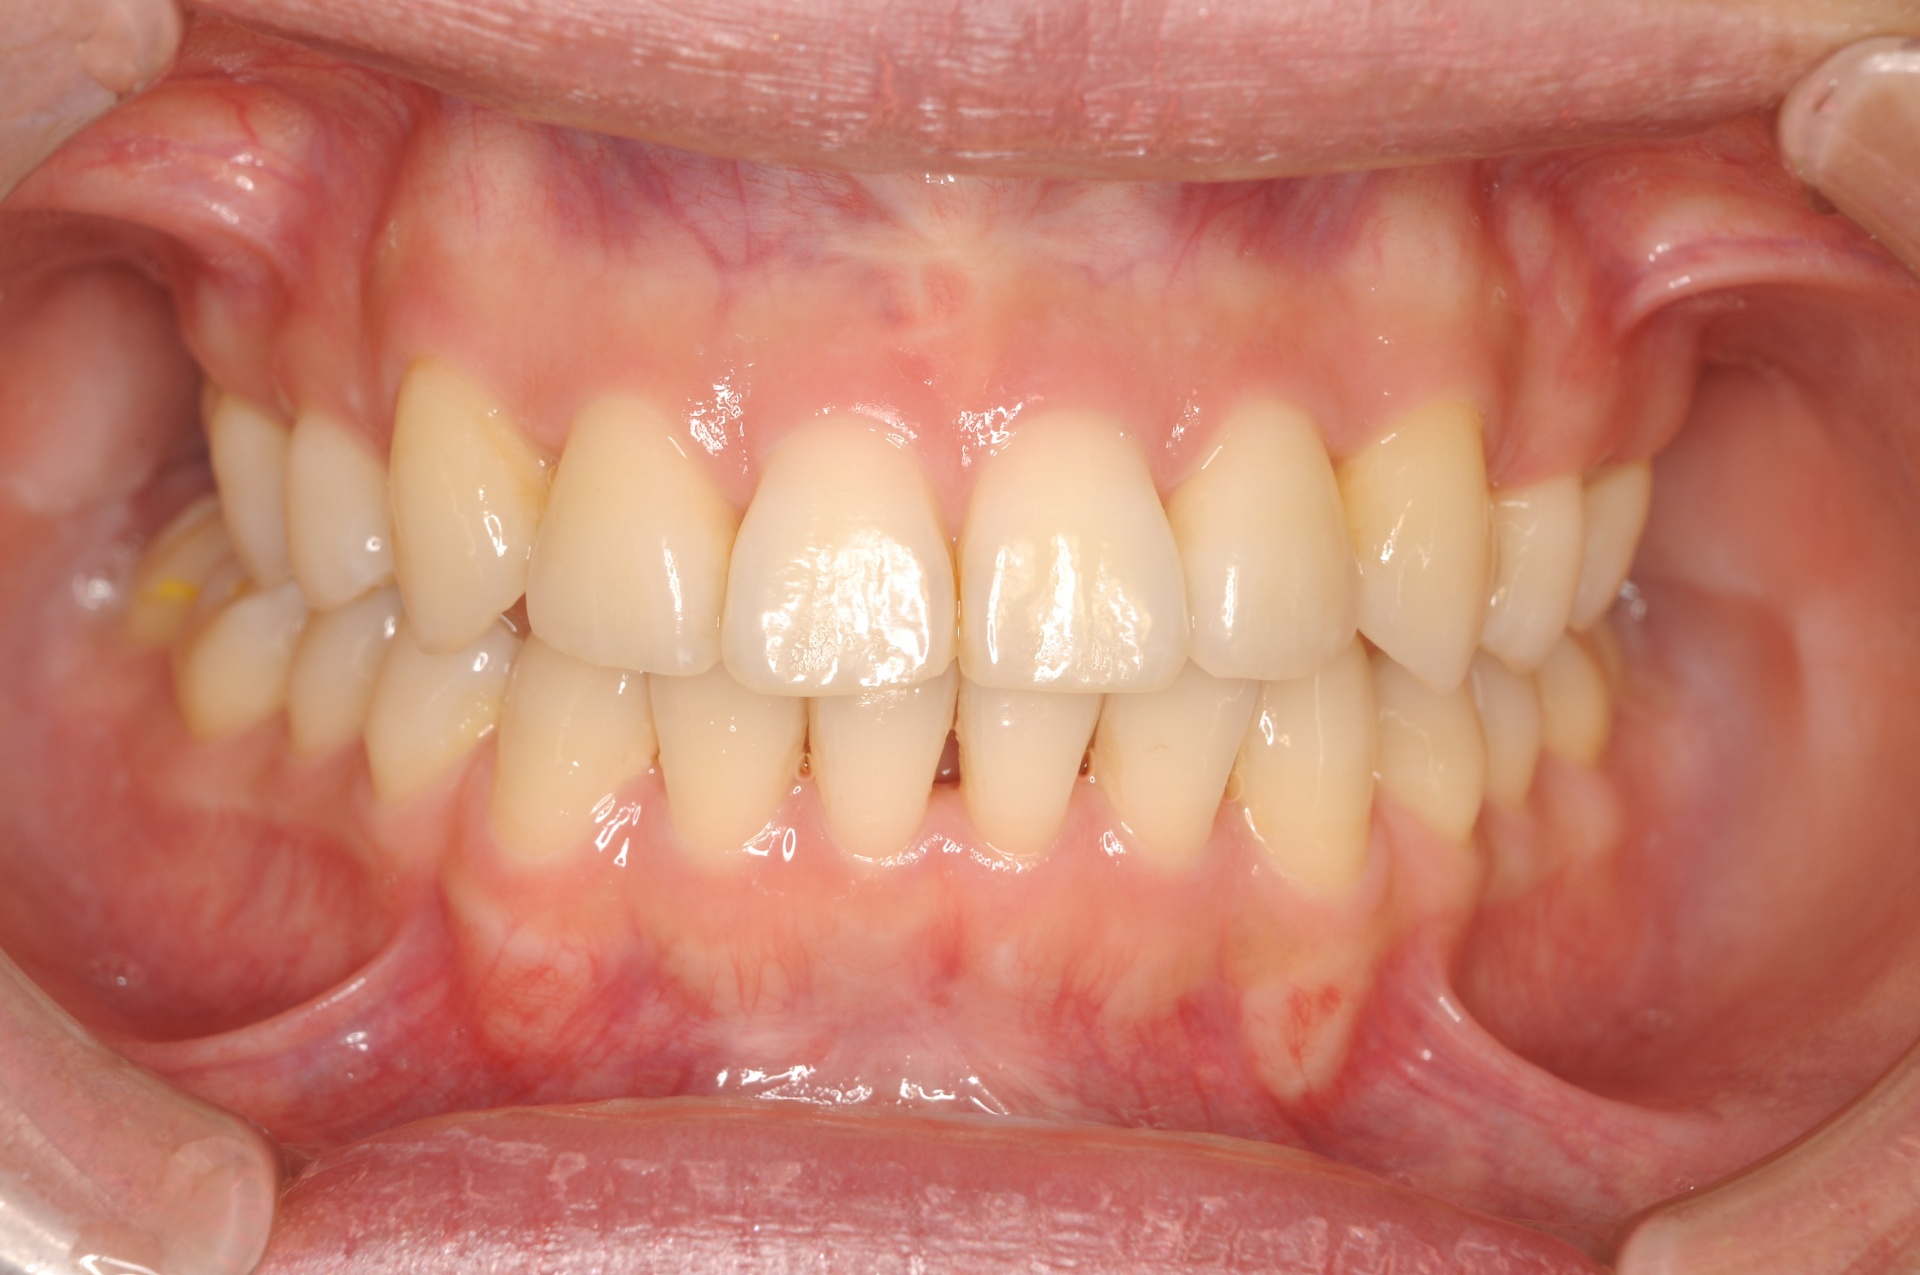

治療後

上下の正中は一致し、上顎両側犬歯は歯列内に誘導されました。奥歯の咬合関係は緊密で、再配列されたことにより機能・審美ともに改善されました。